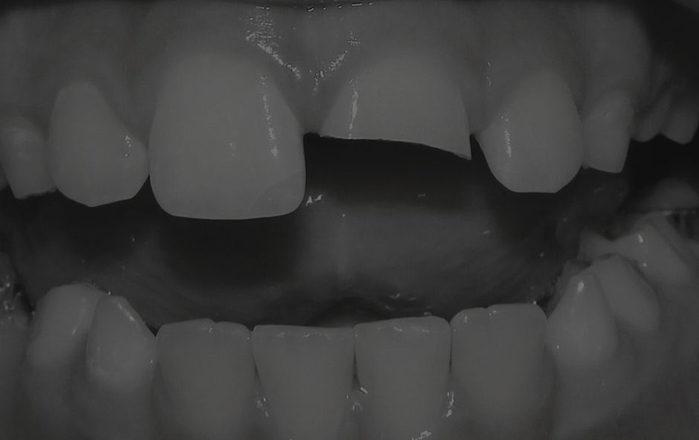

Dental Trauma and Orthodontic Interactions (Live Course)

A significant proportion of the population under 30 receive or have received orthodontic treatment but sadly dental trauma due to vehicular, cycling and E scooter accidents, sporting injuries, skateboarding, assaults …